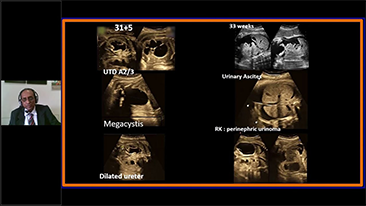

Geburtshilfe